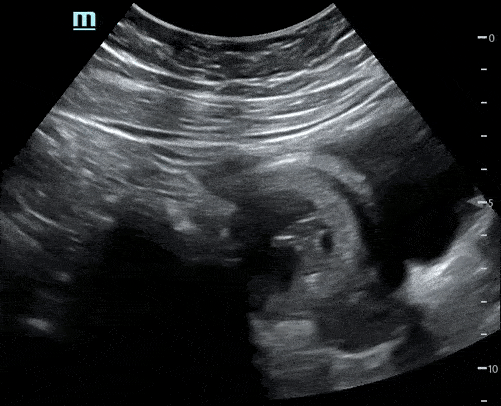

A focused bedside ultrasound was also performed:

The patient was diagnosed with an intrauterine pregnancy with subchorionic hemorrhage. Given her normal vital signs and stable bleeding, she was discharged home with return precautions and recommendations for OBGYN follow up.